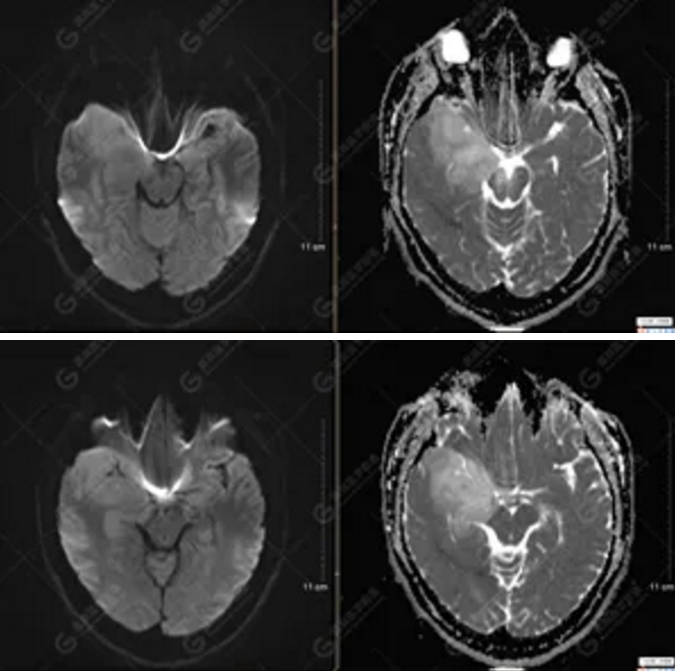

【MRI平掃及增強(qiáng)檢查所見(jiàn)】右側(cè)額顳島葉、右側(cè)海馬及右側(cè)基底節(jié)區(qū)見(jiàn)一團(tuán)塊狀異常信號(hào)影,累及右側(cè)下丘腦及視交叉,大小約5.1cm×4.5cm×4.3cm,呈長(zhǎng)T1長(zhǎng)T2信號(hào),F(xiàn)LAIR序列呈等、稍高信號(hào),DWI序列呈稍高信號(hào),ADC圖高信號(hào),增強(qiáng)后無(wú)明顯強(qiáng)化;病灶周?chē)?jiàn)片狀長(zhǎng)T1長(zhǎng)T2水腫信號(hào)影,F(xiàn)LAIR序列呈高信號(hào),病灶內(nèi)見(jiàn)右側(cè)大腦中動(dòng)脈穿行。余腦實(shí)質(zhì)內(nèi)未見(jiàn)局灶性信號(hào)異常,增強(qiáng)后未見(jiàn)異常強(qiáng)化。右側(cè)側(cè)腦室輕度受壓,余腦室、腦池大小、形態(tài)均正常,中線(xiàn)結(jié)構(gòu)居中

1.右側(cè)額顳島葉、右側(cè)海馬及右側(cè)基底節(jié)區(qū)占位病變,考慮為彌漫性星形細(xì)胞瘤可能性大,累及右側(cè)大腦中動(dòng)脈、右側(cè)下丘腦及視交叉;

彌漫性星形細(xì)胞瘤(WHO Ⅱ級(jí))。